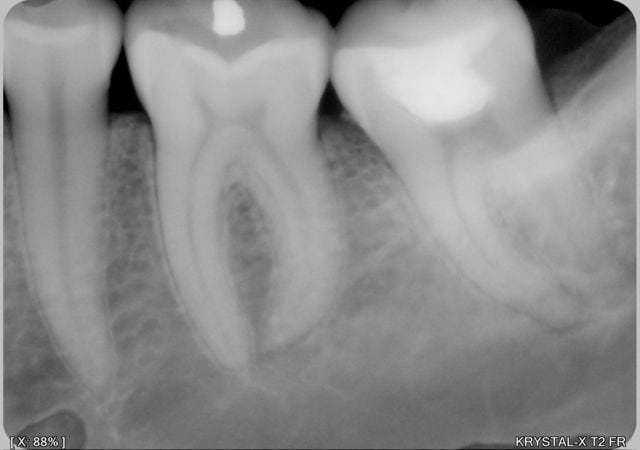

pendant que d'autres etaient en week end .....

005 vxfrtt - Eugenol

007 r9kvdp - Eugenol

009 kqiu0l - Eugenol

hallboy

24/05/2009 à 03h12

muy Zoli!!

quelle sequence d'instruments?

24/05/2009 à 03h20

très joli !

séquences instruments et techniques d'obturation ?

Joli en 2D...

Faut une radio dans 6 mois...

joli boulot, j'aimerais bien apprendre à négocier comme tu l'as fait, les crochets apicaux...

Oui, moi aussi, beau boulot joe1 !

J'ai aussi eu toujours du mal à négocier ce genre de trucs. En général, avec un peu de bol, on arrive à passer la 10. Et puis, en bataillant un peu, parfois on arrive à passer la 15. Mais ça demande moulte précourbage, et trente secondes de recherche à chaque fois qu'on essaye de repasser la lime... Le problème, c'est que si on veut arriver à passer un F1, même manuel, il faut élargir le foramen et tout éclater... Enfin moi je ne sais pas faire autrement !

j'ai preparé longtemps avec les protaper avant les crochets apicaux en irrigant beaucoup avec passage de la lime k 8 pour garder la perméabilité apicale puis lime k 8 10 a l'apex puis protaper manuels s1 s2 et verifier 20(qui est en fait un profile 4 pour cent beaucoup plus flexible qu'un F1)

obturation thermafil 20 en mesial et 25 en distal